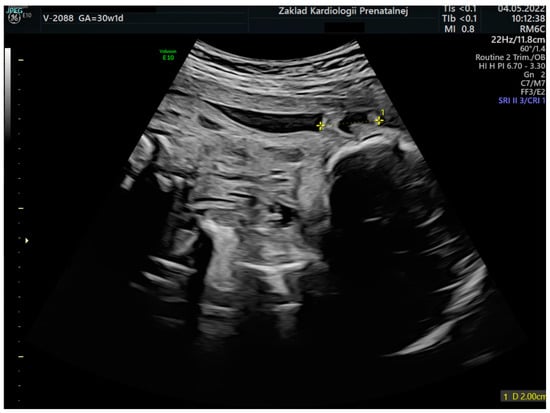

An image of a fetal ear in 2D ultrasound examination. Measurement of the fetal ear at the gestational age of 30 weeks and 1 day.

Figure 8.